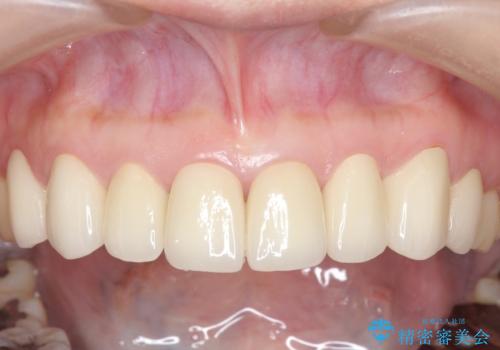

- 前歯の色や形を全体的に綺麗したいといらっしゃった方の症例です。

上顎は左側 4 番目から右側 4 番目までの 8 歯をオールセラミッククラウンで補綴しました。

今回用いたオールセラミッククラウンはジルコニアフレームという白い素材の上にセラミックを盛っているため、審美性が非常に高いのが特徴です。

また、ジルコニアは人工ダイヤモンドの材料にも使われているほど高い強度を持っており、そのためオールセラミッククラウンは審美性だけでなく、奥歯やブリッジの補綴も可能とするクラウンです。